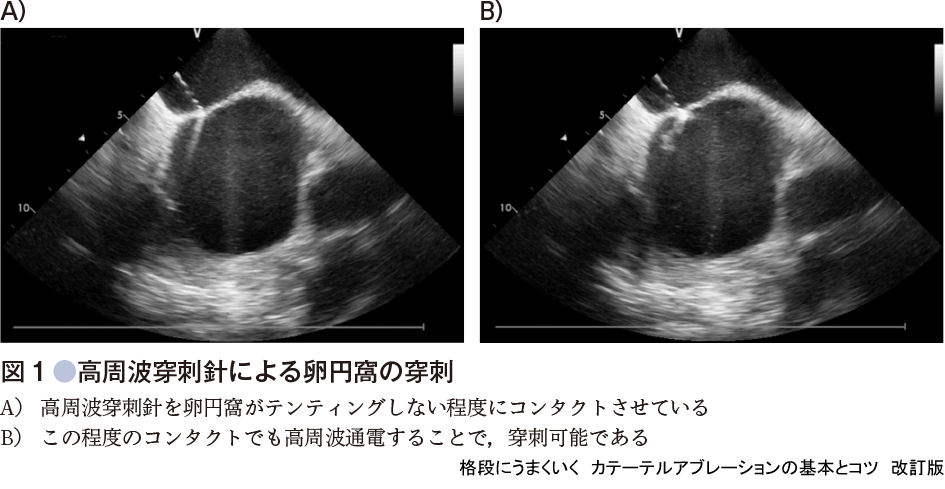

b)高周波穿刺針による心房中隔の穿刺

心房中隔穿刺に金属針を使用すると,穿刺部位で針を押した際に,針先が卵円窩上で滑ることがある.またフロッピータイプの卵円窩の場合は針を押しても,卵円窩が伸びるだけで穿刺できないこともある.一方,高周波穿刺針は針先を卵円窩に軽く接触させ通電しただけで穿刺可能であり(図1),安全性は高周波穿刺針の方が高い.また,高周波穿刺針のカーブの種類には標準と大があり,多くの日本人には標準が適する.しかし,卵円窩の位置は人により大きく異なるので,標的部位に針が当たるように高周波穿刺針の先端のカーブの曲がりを調整する必要がある(図2).